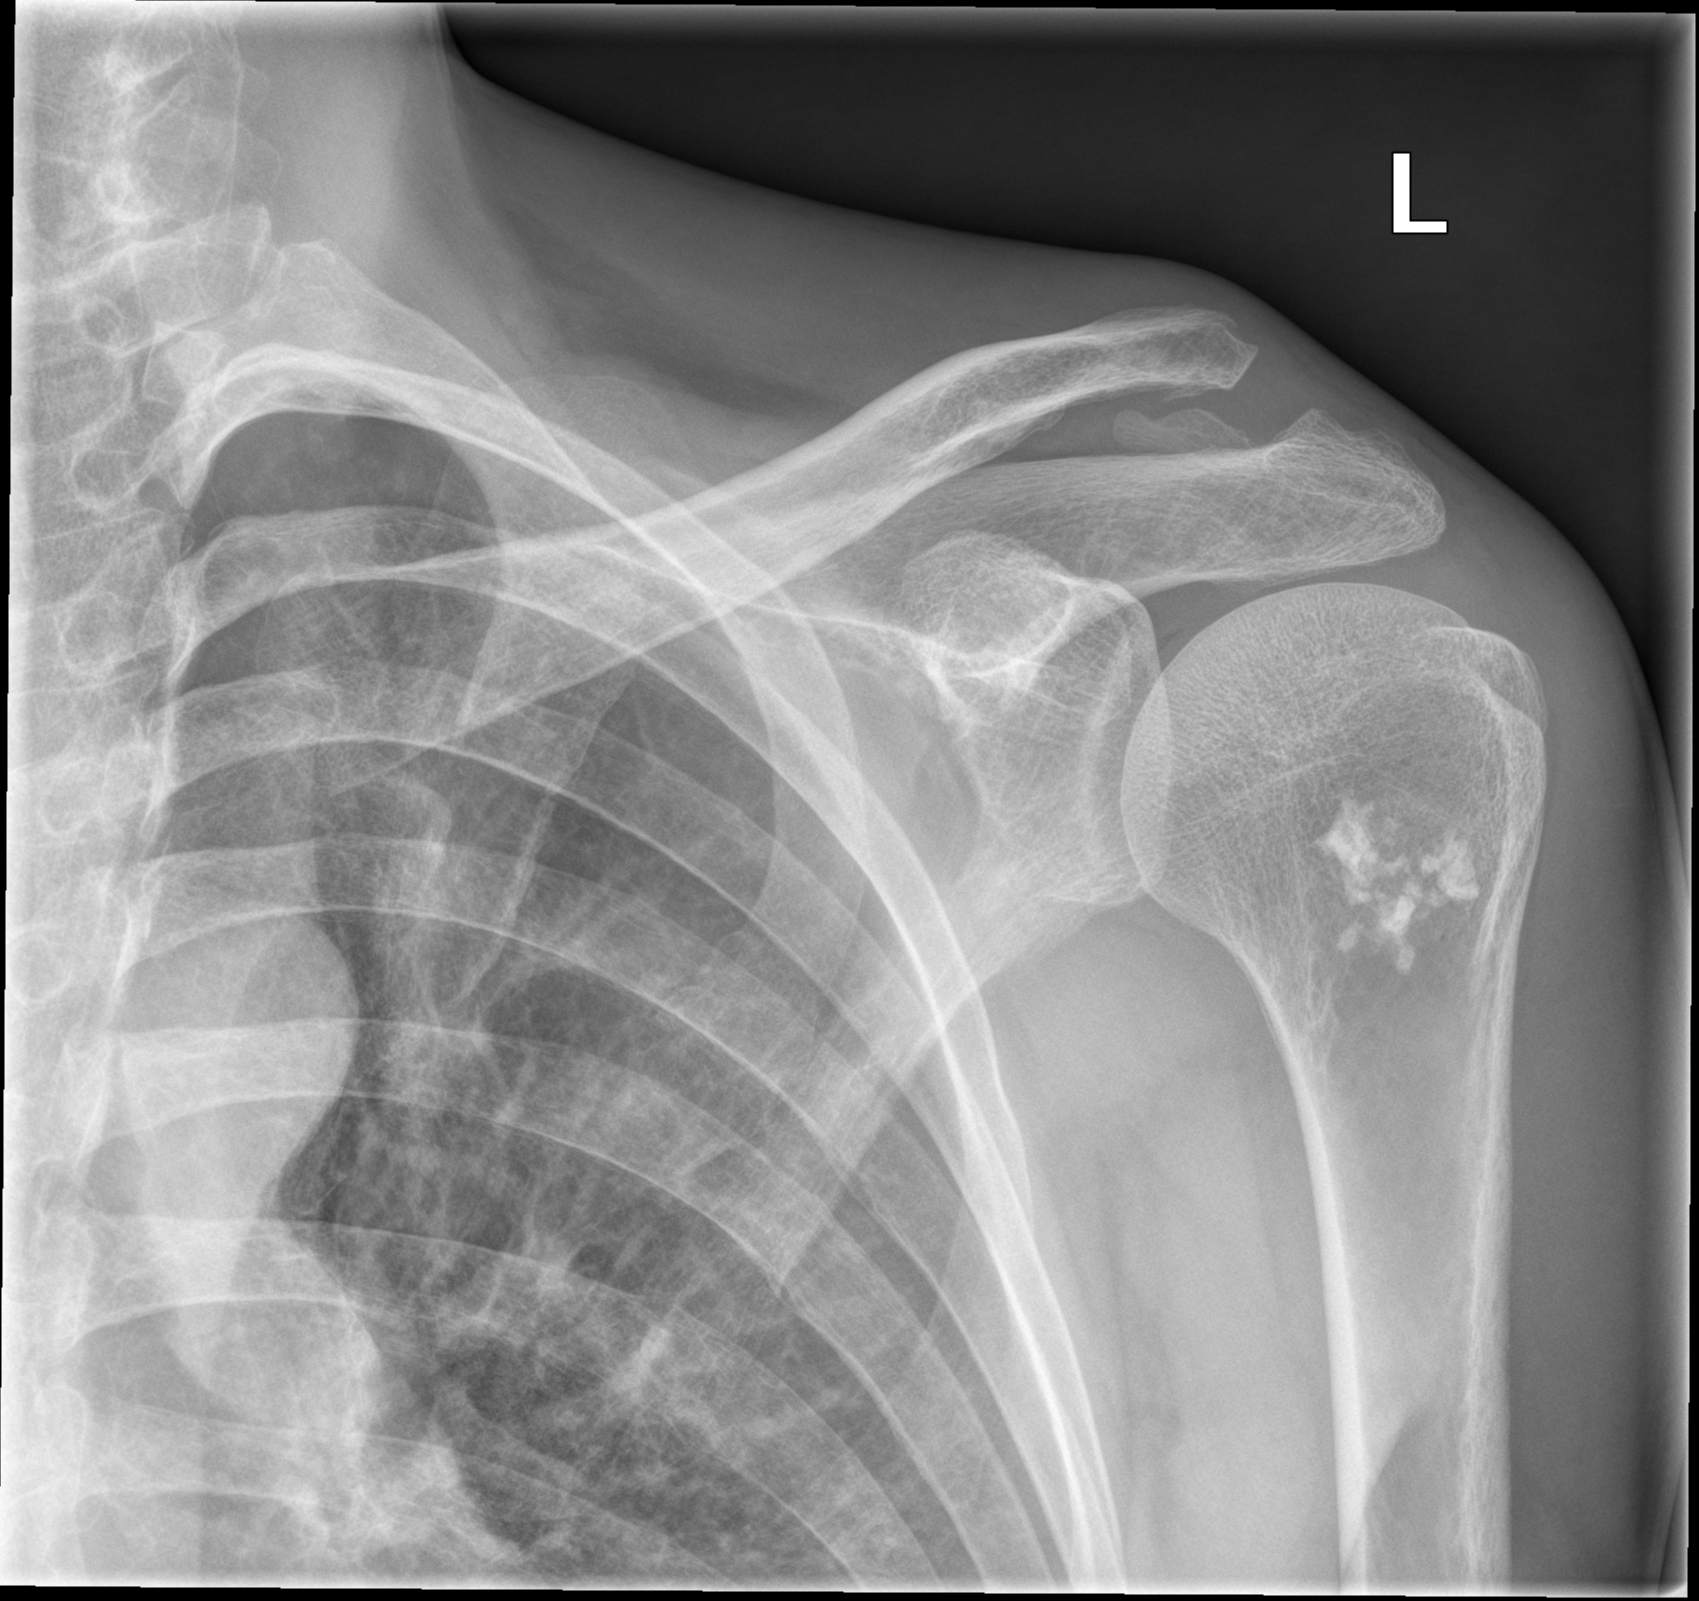

Рентгеновские снимки саркомы плечевого сустава